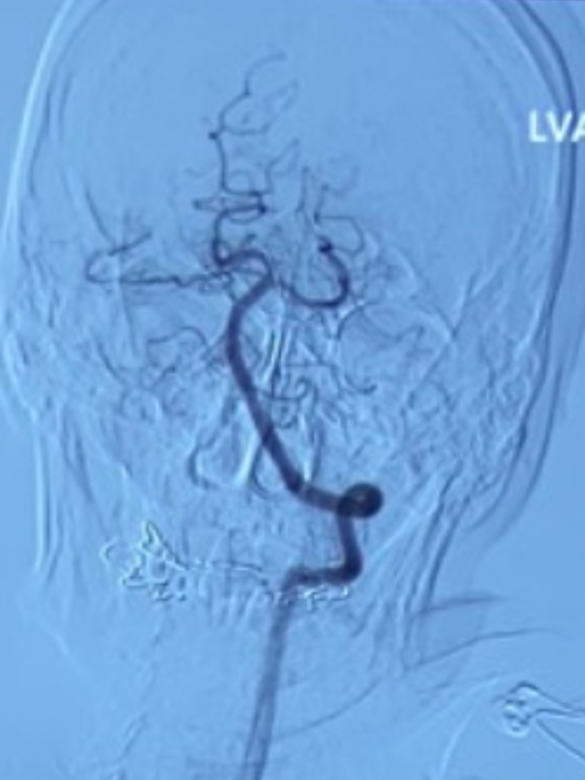

左侧椎动脉正位造影:可见双侧大脑后动脉显影良好,且右侧大脑后动脉通过软膜吻合向右侧大脑中动脉支配区域供血(箭头示)。